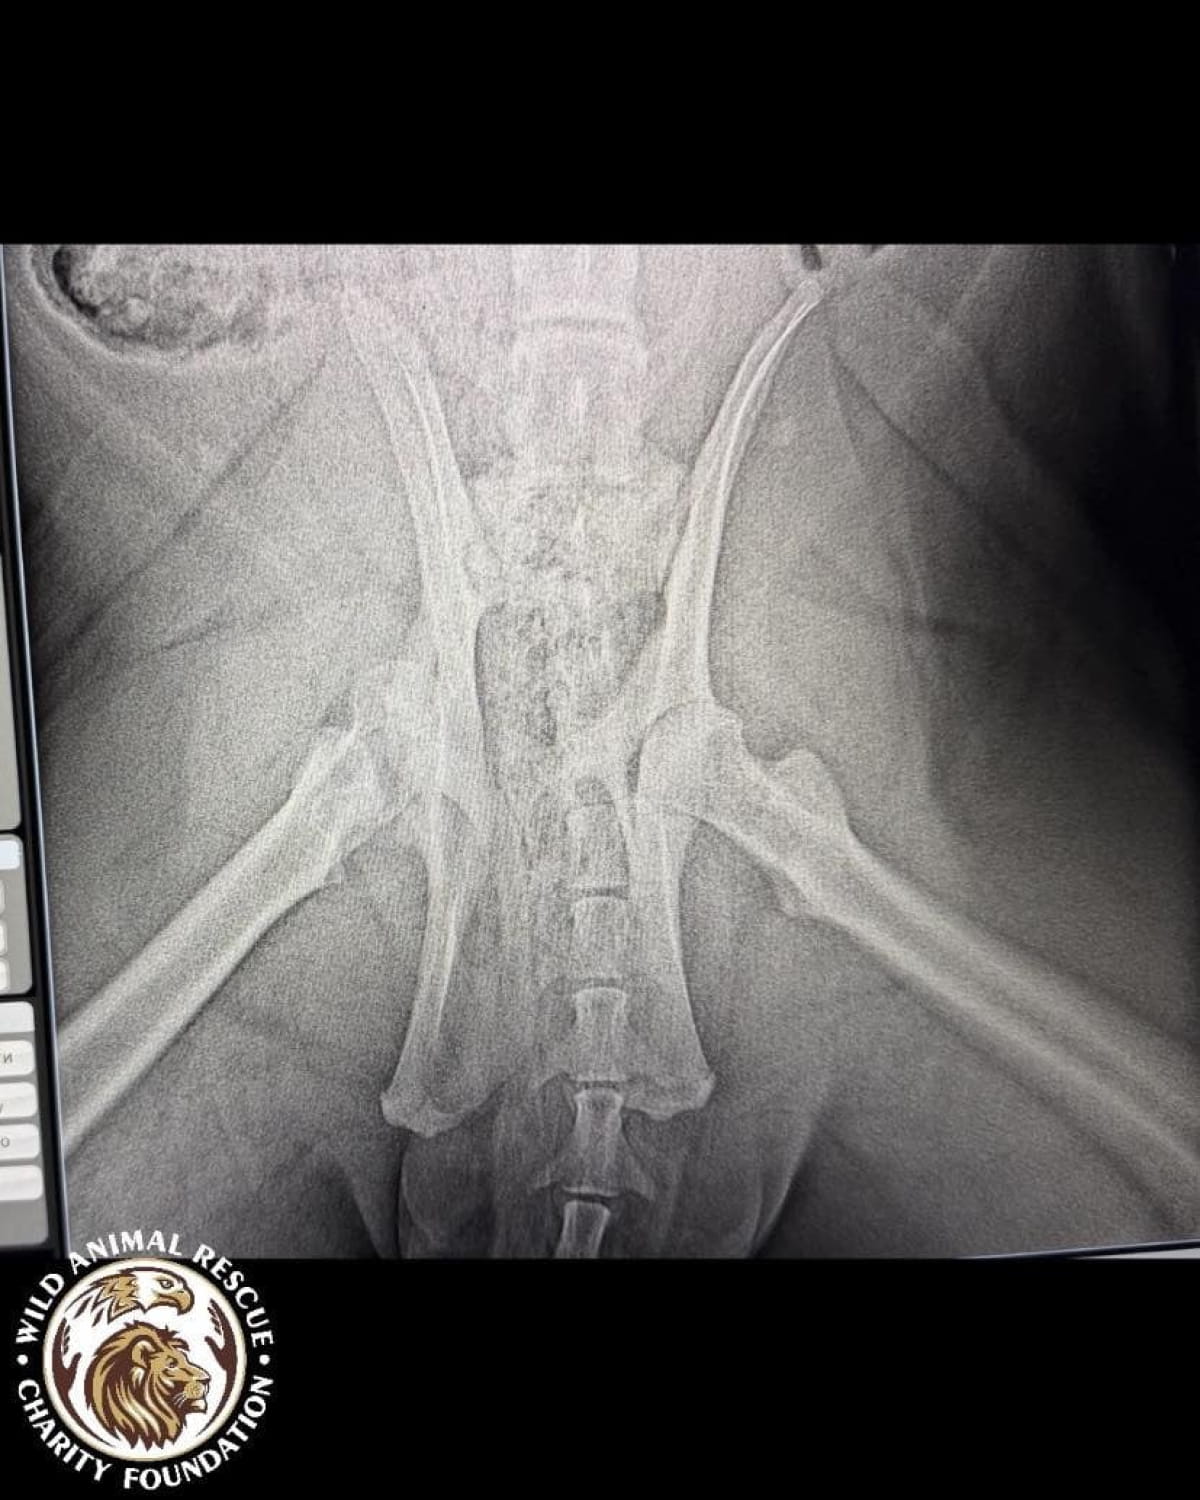

Тварині лише рік, але вона вже стала глибоким інвалідом. Тигриця не здатна самостійно підвестися і ледве пересувається, спираючись виключно на передні лапи. Після ретельного обстеження ветеринари були шоковані станом кісток молодого хижака.

• Критична атрофія м’язів та рахіт.

• Дегенеративні зміни у хребетному стовпі.

• Загальна деформація кісток скелета.

• Двобічна дисплазія кульшових суглобів.

• Остеоартроз та патологічне ремоделювання головки стегнової кістки.